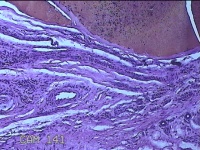

左侧中指皮下结节

性别

女

年龄

32岁

临床诊断

皮下结节

一般病史

发现左侧中指皮下结节1年余。

标本名称

大体所见

灰白暗红色肿物0.5x0.3x0.2cm两个,表面糜烂。